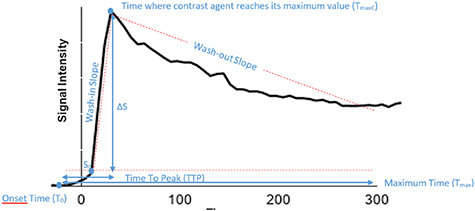

2.6. Perfusion parameters

A linear interpolation to a 1 s time stamp was performed on the signal-time curves followed by a non-parametric analysis that directly calculated simple perfusion parameters correlating with the physiology of tissue. The parameters defined in table 2 were subsequently used to perform a direct comparison between reconstructed images with increasing number of motion states. These parameters are illustrated in figure 4 where TTP is the time that contrast agent need to reach its maximum value (TTP = TmaxC–T0) and T0 is the onset time representing the contrast agent arrival in tissue.

Figure 4. Example of signal intensity vs. time curve.